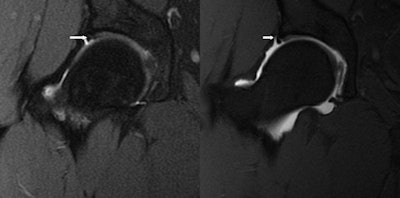

| Image shows a false negative in the case of an acetabular labral tear (arrows) as seen by 3-tesla MRI (left) and MR arthrogram (right). |

There was one false negative on 3-tesla MRI compared with arthroscopy. "Even in that case," Magee said, "when we looked back at the prearthrogram image, we could see the acetabular labral tear in retrospect."

Based on the results, conventional MRI recorded sensitivity of 97% and specificity of 100% for acetabular labral tears compared to arthroscopy. For MR arthrography, both sensitivity and specificity were 100% compared to arthroscopy.